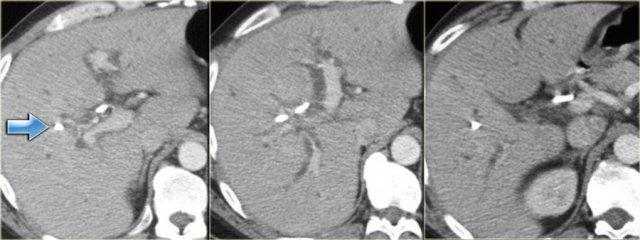

Hình ảnh CT

Trên CT, gan trông khá bình thường.

Tuy nhiên, nếu quan sát ống mật chủ ở vùng đầu tụy, bạn sẽ nhận thấy vùng tỷ trọng mô mềm.

Chẩn đoán phân biệt bao gồm sỏi kẹt hoặc ung thư đường mật, nhưng vì bệnh nhân này không có tắc nghẽn, tình trạng này được cho là do thành ống mật dày lên.

Thành túi mật cũng dày lên.

Bên trái là hình ảnh của một bệnh nhân có bệnh nặng hơn.

Chúng ta có thể thấy giãn đường mật nhẹ với hình ảnh gián đoạn.

Bên trái là hình ảnh của một bệnh nhân với các dấu hiệu CT rõ ràng hơn.

Hãy quan sát hình ảnh rồi tiếp tục đọc.

Các dấu hiệu bao gồm:

- Giãn không liên tục

- Thành ống mật dày tại vùng cuống gan

- Hạch bạch huyết to